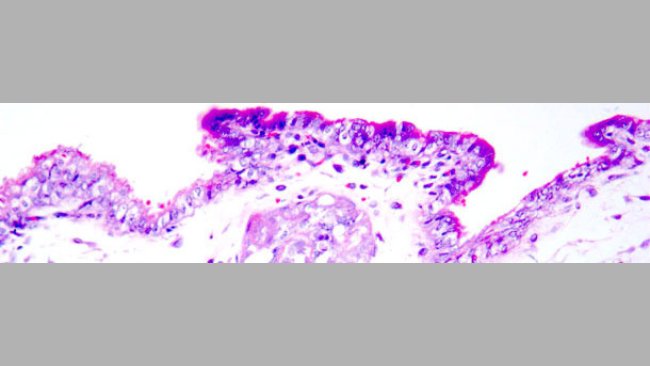

Rozród u loszek inseminowanych nasieniem zanieczyszczonym PCV2. Ochrona loszek szczepionką przeciw PCV2 dla loch.

Szczepienie loszek przeciw PCV2, poprzedzające inseminację nasieniem zanieczyszczonym PCV2 doprowadziło do ograniczenia wiremii, obniżenia siewstwa wirusa oraz ochrony płodów.